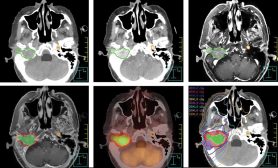

En 2013, considerando que los avances tecnológicos podrían mejorar la seguridad para el paciente, los médicos del MD Anderson comenzaron a utilizar técnicas estereotácticas de reirradiación en pacientes con cánceres recurrentes de cabeza y cuello irresecables. El Dr. Phan y sus colegas visualizan estos tumores creando una imagen tridimensional compuesta a partir de exploraciones mediante resonancia magnética por imágenes, tomografía computarizada y tomografía por emisión de positrones-tomografía computada tomadas con el paciente en la posición de tratamiento. La imagen compuesta se utiliza para planificar la administración de radioterapia corporal estereotáctica (SBRT) con un acelerador lineal o radiocirugía estereotáctica con un bisturí de rayos γ.

Ambas modalidades estereotácticas administran altas dosis de radiación al tumor en muy pocas fracciones—por lo general, de tres a cinco para la SBRT, y de una a tres para la radiocirugía—con mínimas dosis a las estructuras cercanas. Para garantizar la precisión de la acción dirigida, al paciente se le toman nuevas imágenes en la posición de tratamiento antes de cada sesión. La SBRT se utiliza para la mayoría de los tumores de cabeza y cuello, en tanto que la radiocirugía estereotáctica se reserva para tumores pequeños en la base del cráneo.